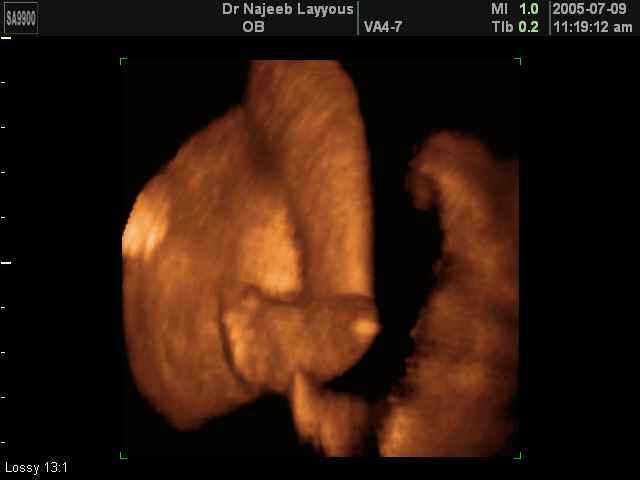

صور طبية للحمل بجهاز الالتراساوند | الدكتور نجيب ليوس